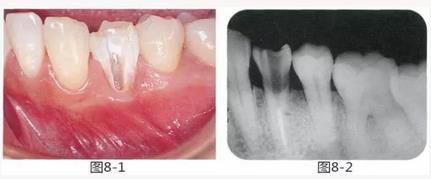

圖8-1 左下4頰側(cè)牙頸部有齦下齲壞,最終拔牙。齦下還殘留著感染的牙體組織。

圖8-2 左下4的X光照片。如果在此狀態(tài)下切除牙槽骨,就必須要犧牲鄰牙的支撐骨。